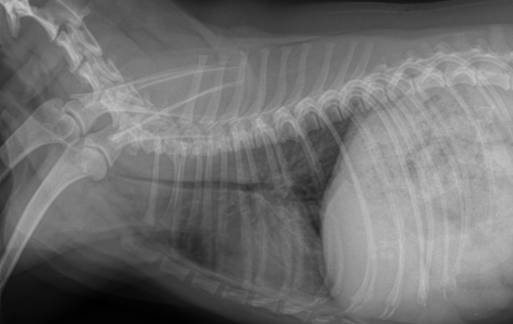

И после стентирования:

Профилактики непосредственно коллапса нет — это генетическое заболевание. Но можно постараться избежать осложнений. Отличной профилактикой является отказ от ошейника, который при рывке и натягивании собакой поводка давит на трахею, вызывая кашель, а кашель в свою очередь может вызвать прогрессирование заболевания. Так же профилактикой является своевременная диагностика и лечение заболеваний верхних дыхательных путей, аллергии, вирусных и инфекционных заболеваний.